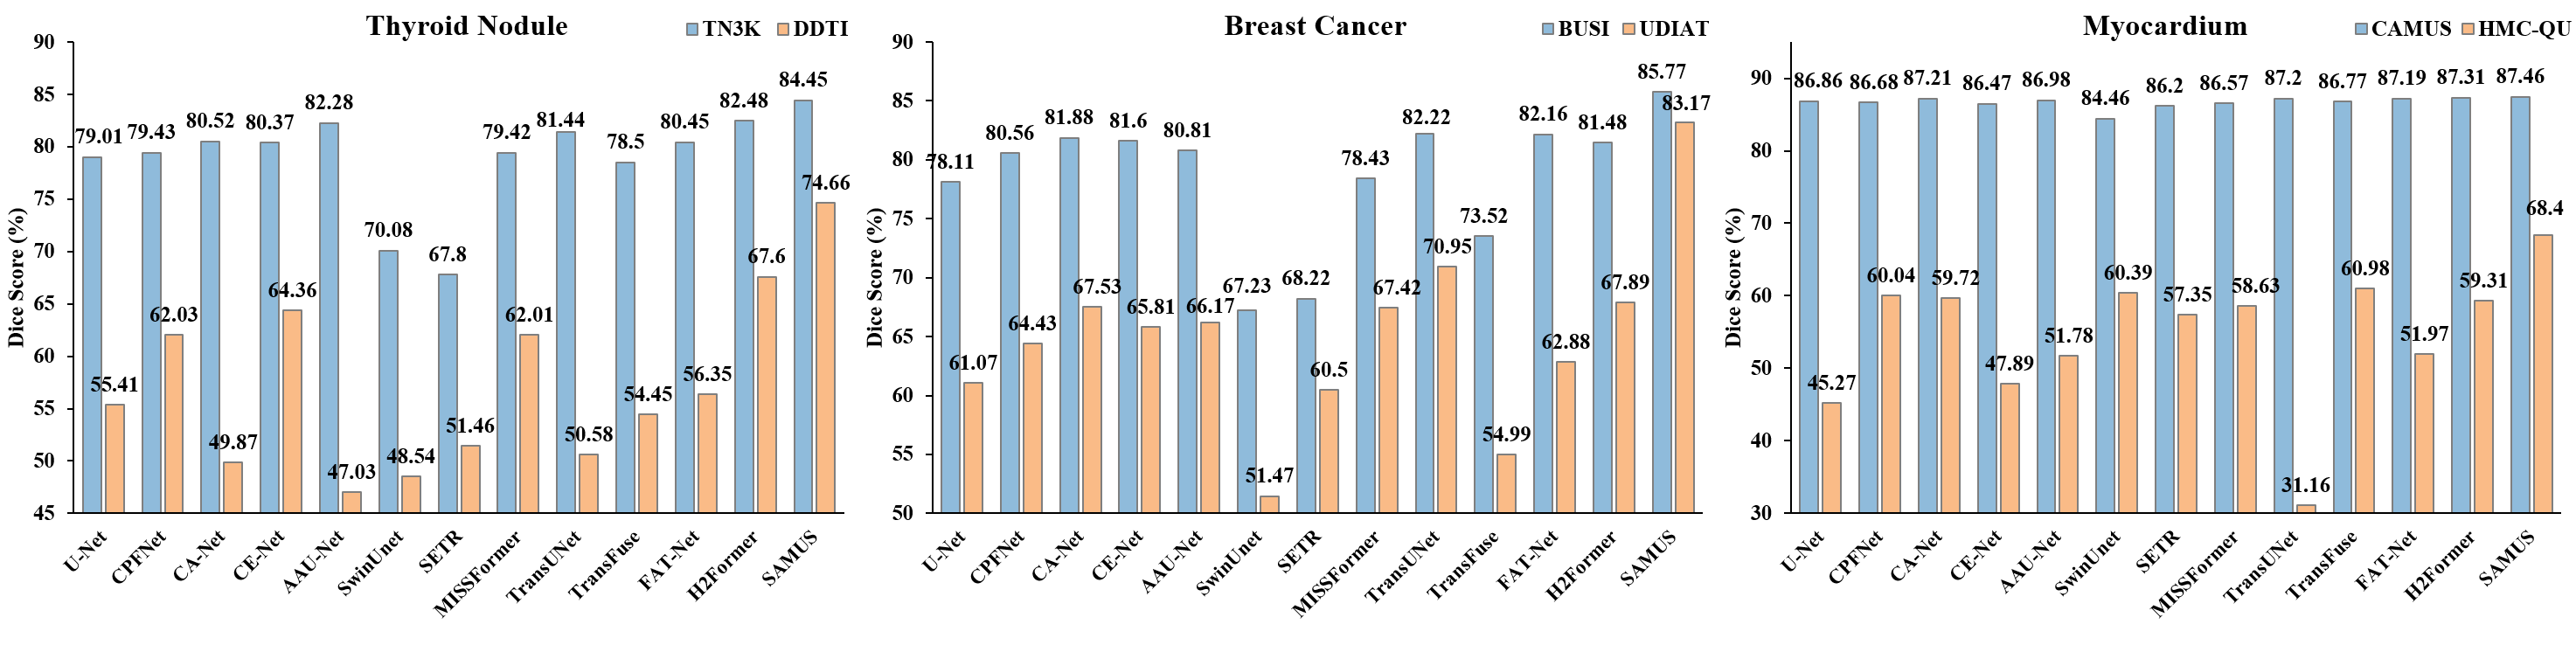

Quantitative results: Quantitative results of different task-specific approaches on TN3K, BUSI, CAMUS-LV, CAMUS-MYO, and CAMUS-LA are summarized in Table 7. Among these state-of-the-art approaches, H2Former achieves the best performance on TN3K and CAMUS-MYO, leading to the average Dice scores of and respectively. TransUnet, CA-Net, and FAT-Net achieve the best performance on BUSI, CAMUS-LV, and CAMUS-LA respectively, with the average Dice scores of , , and . Comparatively, SAMUS consistently achieves better performance on all five tasks including TN3K, BUSI, CAMUS-LV, CAMUS-MYO, and CAMUS-LA with the average Dice scores of 84.45, 85.77, 93.73, 87.46, and 91.58 respectively. It validates the effectiveness of adapting SAM to the medical image domain by SAMUS.

Generalization ability: Quantitative comparison on the generalization performance of different task-specific methods is illustrated in Fig. 3. Among comparison methods, H2Former, TransUNet, and TransFuse achieve the best performance on DDTI, UDIAT, and HMC-QU respectively. Comparatively, SAMUS surpasses the best comparison method on each dataset with an average increase of , , and in Dice respectively. Comparing the performance between seeable and unseen datasets, SAMUS encounters the least performance degradation in contrast to other comparison methods across three different segmentation tasks. One interesting observation is that on the breast cancer segmentation task, the performance of SAMUS on the unseen dataset (i.e., UDIAT) is even better than that of the best comparison method on the seeable dataset (i.e., BUSI). It demonstrates the exceptional generalization ability of SAMUS in handling unseen domains, showcasing its robustness and adaptability across diverse medical image segmentation scenarios.

Generalization ability: Comparison of different foundation models on unseen domains is summarized in Fig. 6. In general, the generalization performance of foundation models trained on US30K in the medical image segmentation tasks is far better than that of the original SAM. In terms of the three pairs of segmentation tasks, namely thyroid nodule segmentation, breast cancer segmentation, and myocardium segmentation, all foundation models encounter severe performance degradation on myocardium segmentation and generalize well on breast cancer segmentation. SAMUS consistently achieves the best performance across all three unseen datasets, leading to superior Dice scores of , , and for the segmentation of thyroid nodule, breast cancer, and myocardium, respectively. It underscores the exceptional generalization ability of SAMUS, outperforming other foundation models consistently and substantially on unseen domains.